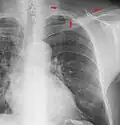

A chest radiograph, chest X-ray (CXR), or chest film is a projection radiograph of the chest used to diagnose conditions affecting the chest, its contents, and nearby structures. Chest radiographs are the most common film taken in medicine.

Different views (also known as projections) of the chest can be obtained by changing the relative orientation of the body and the direction of the x-ray beam. The most common views are posteroanterior, anteroposterior, and lateral. In a posteroanterior (PA) view, the x-ray source is positioned so that the x-ray beam enters through the posterior (back) aspect of the chest and exits out of the anterior (front) aspect, where the beam is detected. To obtain this view, the patient stands facing a flat surface behind which is an x-ray detector. A radiation source is positioned behind the patient at a standard distance (most often 6 feet, 1,8m), and the x-ray beam is fired toward the patient.